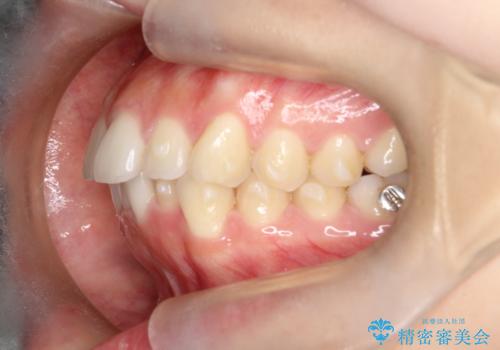

【インビザライン】前歯を下げたい

- 前歯が出ていることを主訴に来院されました。

奥歯を後ろに動かしながらスペースを作ることで、前歯を下げることができ患者さんにも満足していただきました。